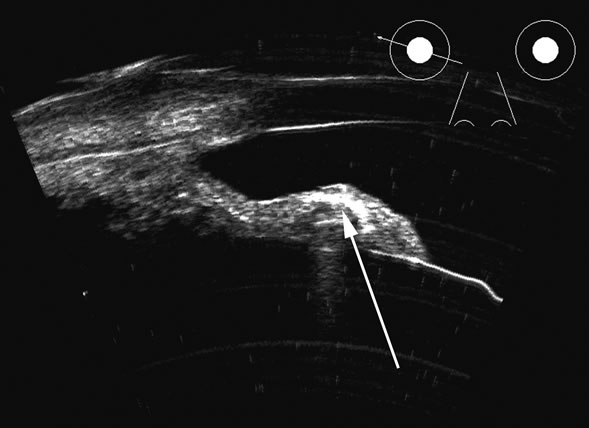

Hypotony is easily diagnosed by direct measurement of intraocular pressure, but the underlying cause is difficult to evaluate.11 High-frequency ultrasound scans can easily reveal separation of the ciliary body and the sclera. This allows different forms of hypotony to be determined—for example: tractional with membrane attached; primary as idiopathic, often inflammatory or hemorrhagic; and dehiscence secondary to iridodialysis or scleral perforation (Fig. 6).

Fig. 6. Hypotony of the eye generally is easily diagnosed by a separation of the ciliary body from the sclera. We have noted several types of such separation, such as tractional, primary (idiopathic), and dehiscence secondary to iridodialysis or scleral perforation, as in filtration procedures. In our series, greater than two clock hours of separation is typical of hypotony. The lower figure shows a concomitant thickening of the retina-choroid complex, also seen in hypotony (arrows). Long-standing hypotony typically has a shortened globe and possible retinal or choroidal separation.